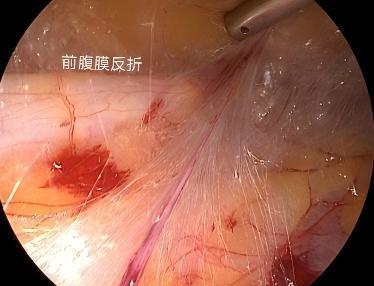

• 新型经脐腹腔镜术与常规三孔法治疗单侧巨大腹股沟斜疝的对比研究

2025, 31(11):67-74. DOI: 10.12235/E20250066

摘要 (60) HTML (24) PDF 2.52 M (60) 评论 (0) 收藏

摘要:目的 探究新型经脐腹腔镜术与常规三孔法治疗单侧巨大(≥15 mm)腹股沟斜疝的临床疗效。方法 回顾性分析2020年7月-2023年8月该院收治的213例单侧巨大(≥15 mm)腹股沟斜疝患儿的临床资料。按照手术方法不同,将患儿分为三孔组(107例,行三孔法腹腔镜疝囊高位结扎术)和新型组(106例,行新型经脐腹腔镜术)。比较两组患儿手术指标、儿童疼痛行为量表(FLACC)评分、家长对切口外观满意度、睾丸体积、术后并发症和复发率(术后1年内)。结果 新型组术中出血量和切口数量少于三孔组,切口长度、手术时间、术后切口愈合时间和住院时间短于三孔组,差异均有统计学意义(P < 0.05);术后6、12、24和48 h,新型组FLACC评分低于三孔组,差异均有统计学意义(P < 0.05);新型组患儿家长对切口外观满意度为100.00%,高于三孔组的88.79%,差异有统计学意义(P < 0.05);两组患儿术前患侧睾丸体积小于健侧,术后1年,患侧睾丸体积大于术前,差异均有统计学意义(P < 0.05);新型组术后1年健侧与患侧睾丸体积比较,差异无统计学意义(P > 0.05);两组患儿并发症总发生率和总复发率比较,差异均无统计学意义(P > 0.05)。结论 与常规三孔法比较,新型经脐腹腔镜术具有操作便捷、创伤小、疼痛轻、术后恢复快和切口美观等特点,应用于≥15 mm的单侧巨大腹股沟斜疝的治疗中,更具优势。